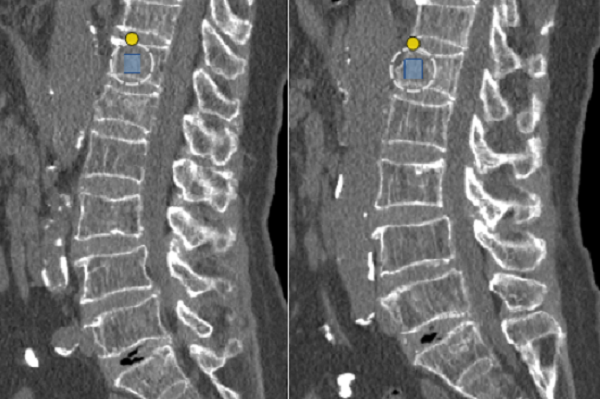

案例一: 一位奶奶扭伤腰后疼痛,做了腰椎CT和骨密度检查。结果显示腰部一节骨头有轻微裂缝,同时骨密度测量值很低,明确诊断为“严重骨质疏松”。这解释了为什么轻轻一扭就会疼痛,也提醒需要及时治疗,预防更严重的骨折。

aza

图片7